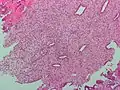

Micrographie montrant la condensation stromale de l'endomètre, observée lors des menstruations.